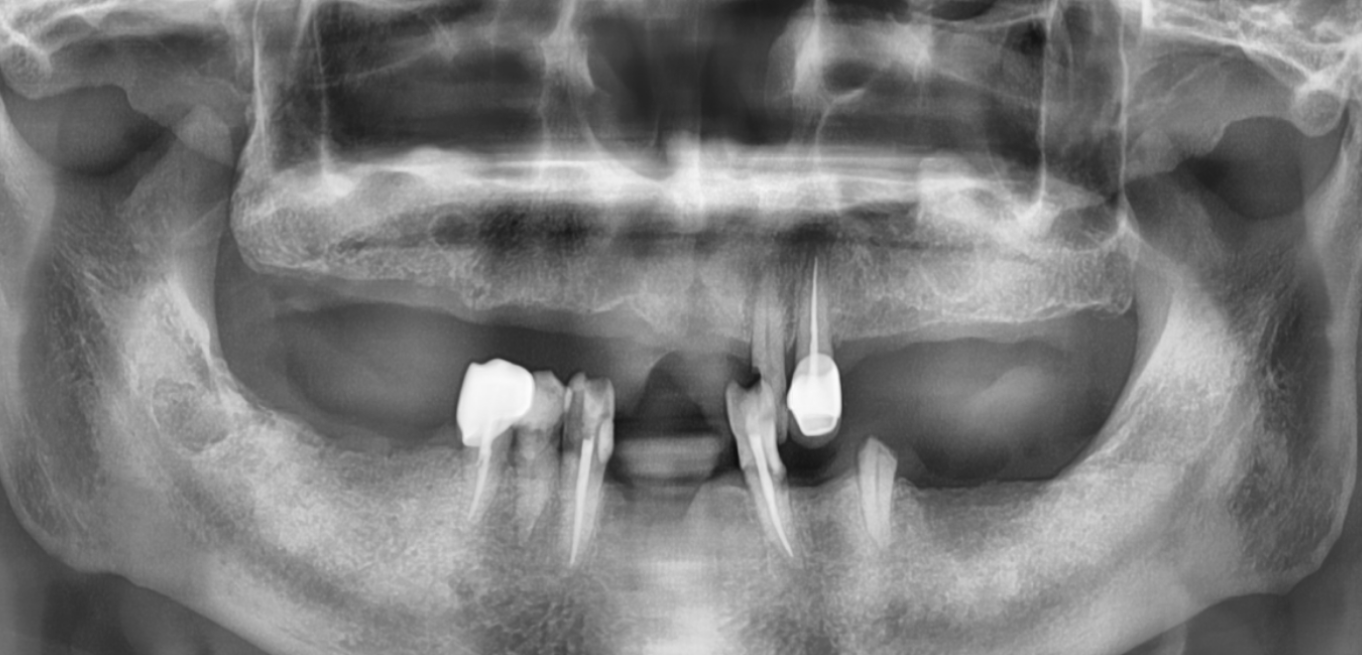

Before & After

Drag Before After

버튼을 움직여서 변화를 확인해보세요.

(서울정석치과는 의료법을 준수하며 위 케이스는 실제 환자의 동의를 얻은 사례입니다.)